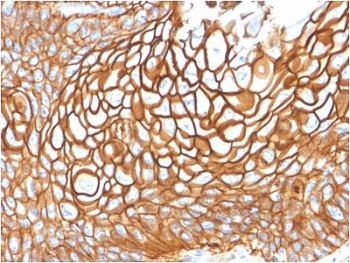

CD63 Antibody / LAMP-3 [orb2637613]

FACS, IF, IHC-P, WB

Human, Mouse

Mouse

Monoclonal

Unconjugated

100 μg